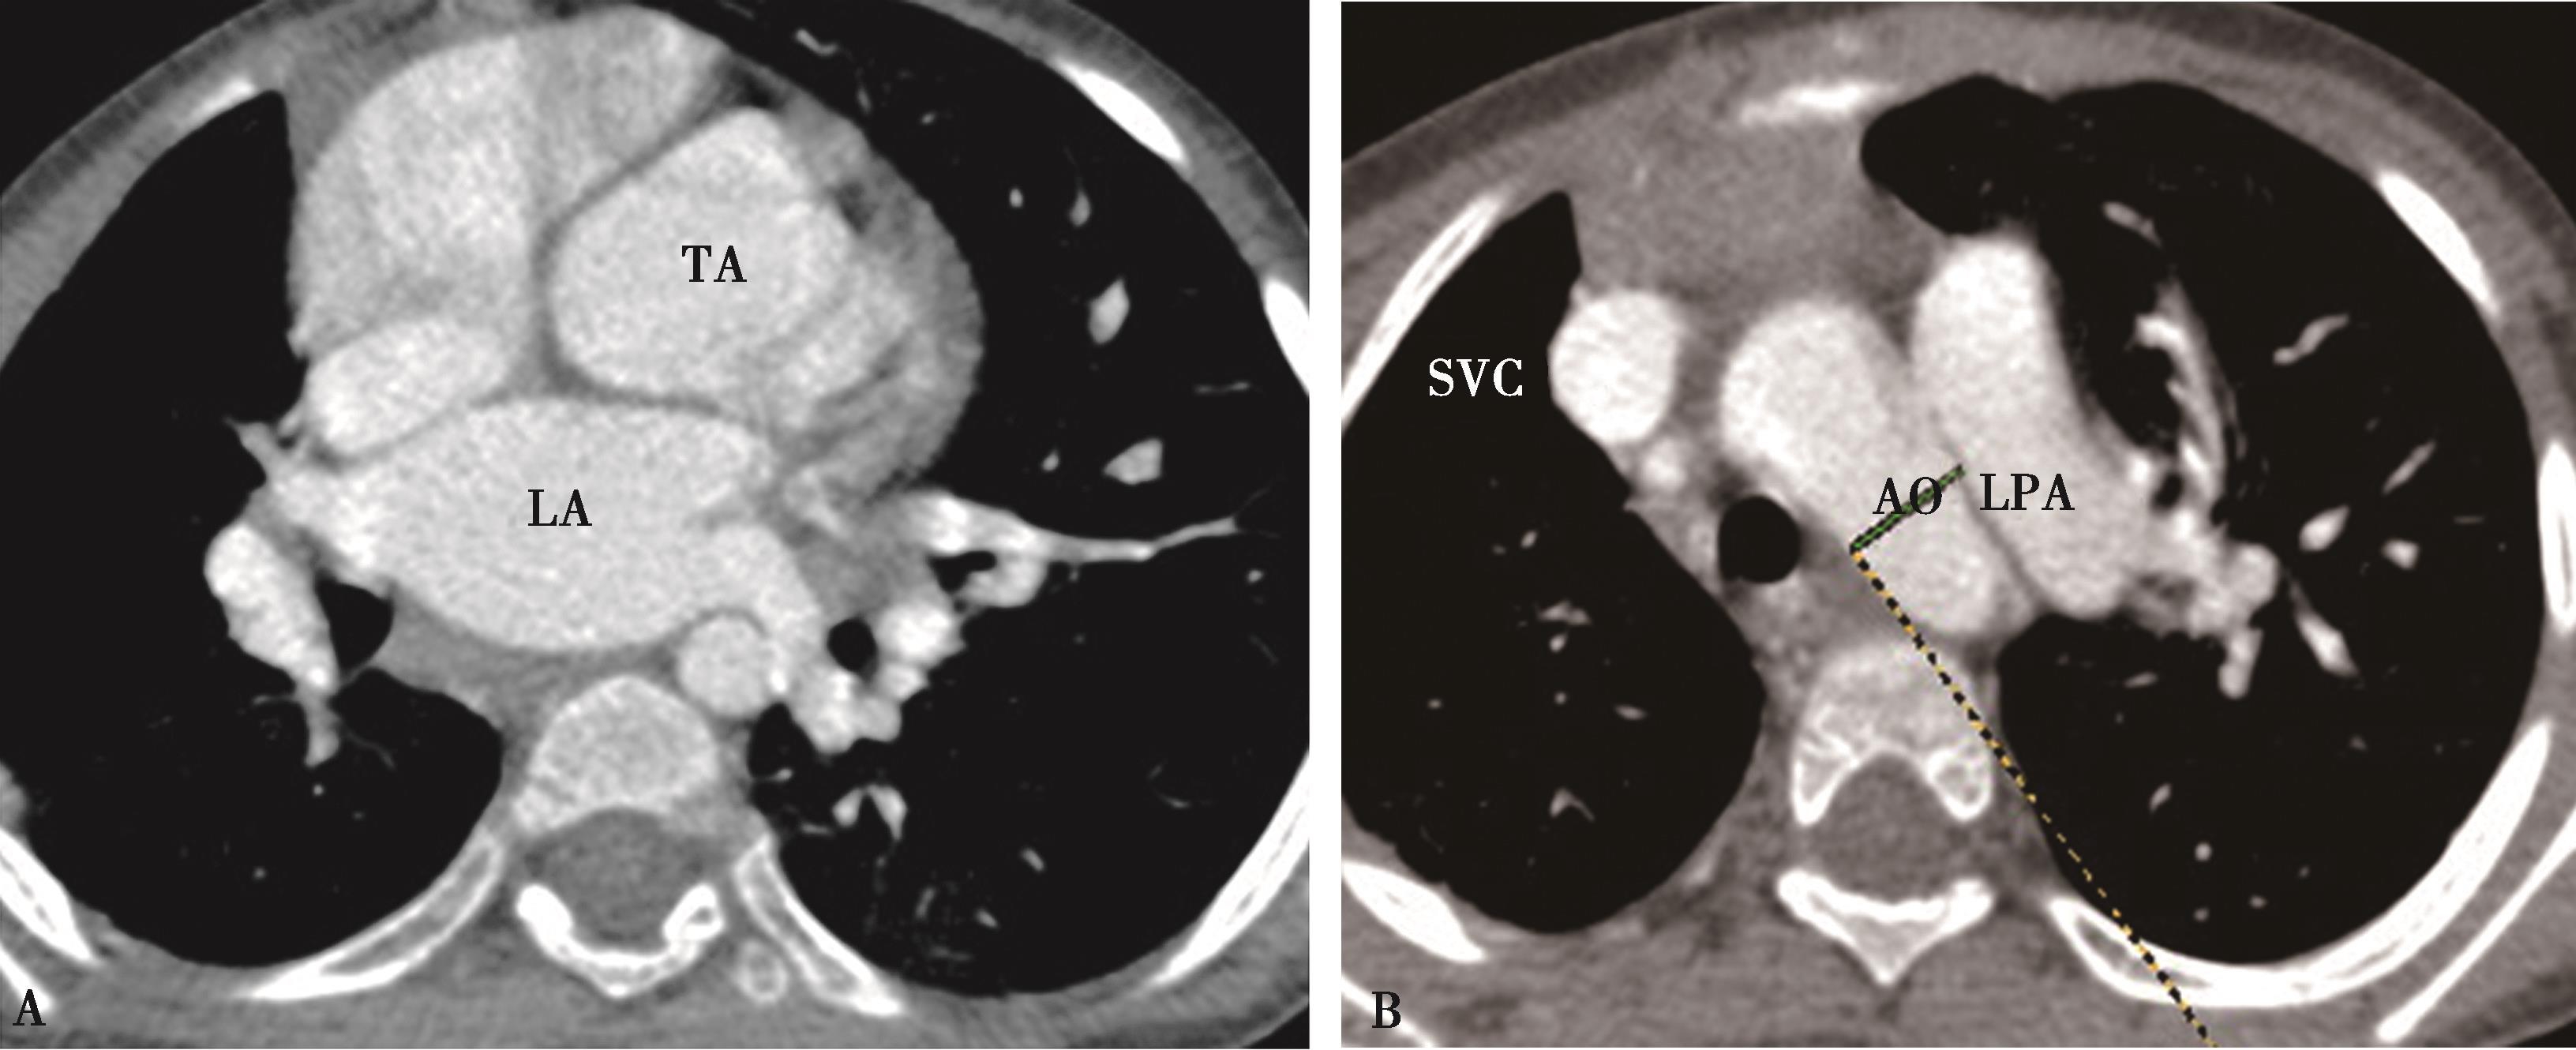

主要显示肺动脉,示中心肺动脉扩展,外围纤细;右心室增大。呈现肺动脉高压征象(图8-12-1)。

图8-12-1 女,54岁,混合型结缔组织病(经临床实验室检查确诊)

A.X线胸片,示两肺透过度降低,广泛间质性改变。肺动脉段凸,右心增大,肺动脉高压;B.CT横断图像,两肺野呈不均匀磨玻璃状改变,间质改变,间质纤维化,可见间隔线,为肺小动脉炎特点;C、D.增强扫描,中心肺动脉高度扩张,外围纤细,右心房室增大,为肺动脉高压改变;左下叶基底段实变容积缩小